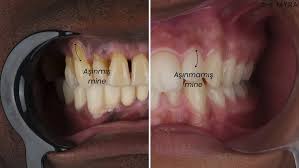

2.3 Yaşlanma

- Yaş ilerledikçe dişeti dokusu doğal olarak incelir.

- Doku kaybı ve dişeti geri çekilmesi, yaşa bağlı değişikliklerle hızlanabilir.